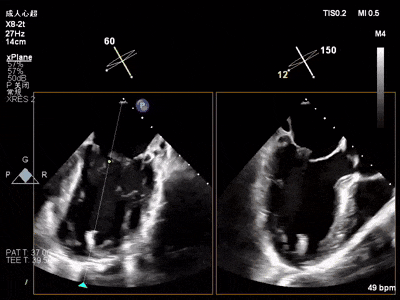

术中超声要点

术前术后对比图

术前

术后

术后,出院检查报告显示夹子位置固定,二尖瓣、三尖瓣及主动脉轻微反流,左房增大,左室内径正常上限,EF值正常下限(WMSI 1分)。